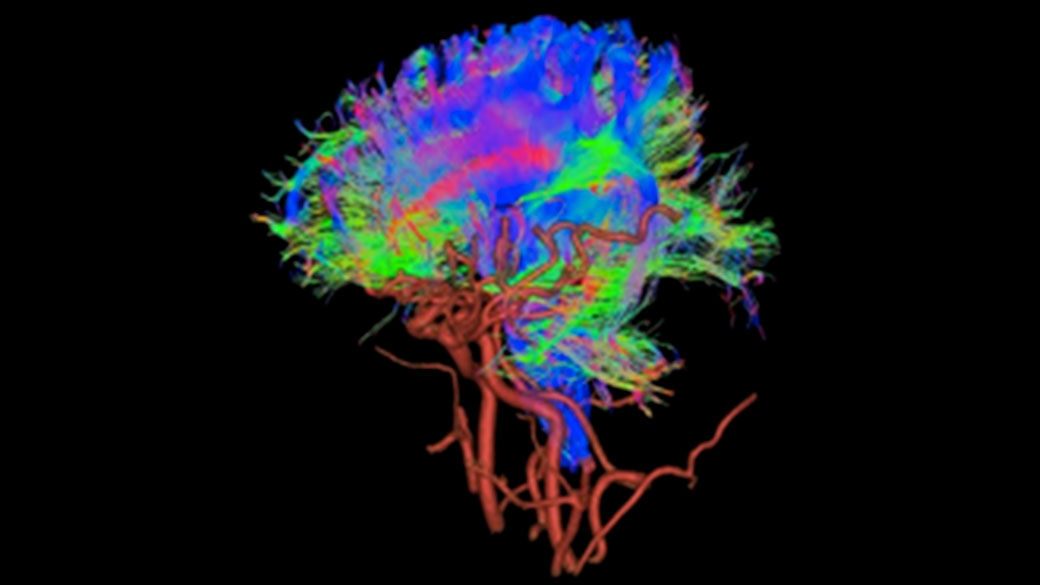

AIR™ Recon DL improves SNR and image sharpness, enabling shorter scan times

Achieve a 25% efficiency gain with Ultra High Efficiency (UHE) gradient system. Fast, clear Total Digital Imaging (TDI) increases SNR by 25%. Improved IQ in 80% of cases without added time. Acquire higher SNR without a time penalty and get images virtually free of artifact with AIR™ Recon DL.***